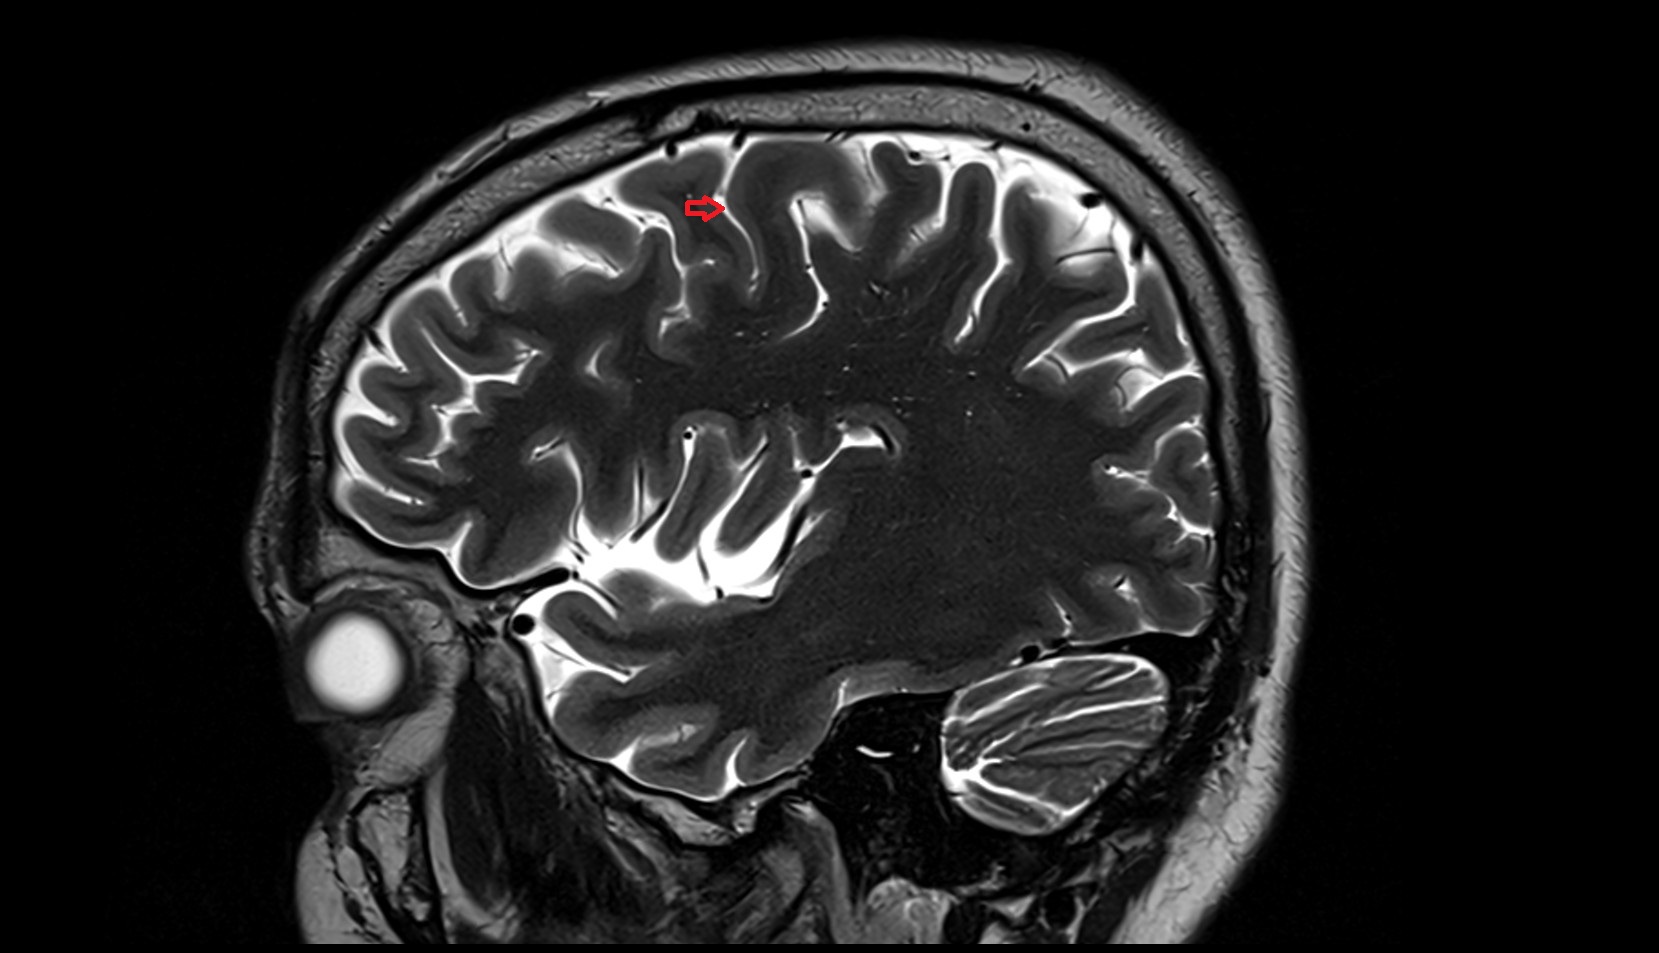

- Central sulcus

- Cistern of central sulcus